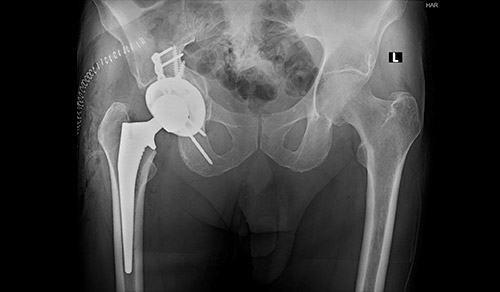

The JAMA study examined trends in mitral valve repair and replacement and explained the benefits of undergoing repair at a high-volume center.